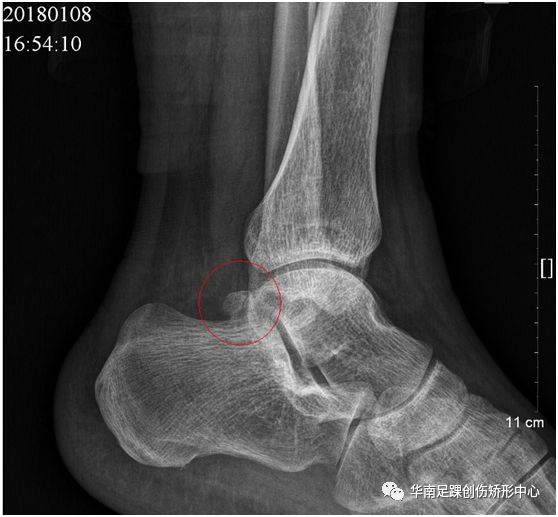

踝骨正常,踝骨骨折

有意义的两张cr片子看懂的点评一下

踝关节撞击综合征关节镜微创治疗

股骨颈骨折▼ 正常胸椎▼ 来源:骨头中外 如有侵权请联系我们删除